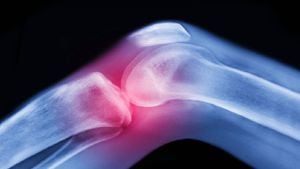

La artritis es la hinchazón y sensibilidad de una o más de las articulaciones, de acuerdo con Mayo Clinic, entidad sin ánimo de lucro dedicada a la práctica clínica, la educación y la investigación.

Adicional, explicó que los principales síntomas de la afección son dolor y rigidez de las articulaciones, que suelen empeorar con la edad. Además, los tipos más frecuentes de esta enfermedad son la artrosis y la artritis reumatoide.

No obstante, Mayo Clinic reveló que si los métodos tradicionales no sirven, los médicos pueden sugerir una cirugía, como:

- Reparación de la articulación. En algunos casos, las superficies articulares pueden repararse o realinearse para reducir el dolor y mejorar la función. Estos tipos de procedimientos suelen efectuarse de manera artroscópica, a través de pequeñas incisiones en la articulación.

- Reemplazo de la articulación. Este procedimiento consiste en extraer la articulación dañada y sustituirla por una artificial. Las articulaciones que se reemplazan con mayor frecuencia son las de caderas y las de rodillas.

- Fusión de la articulación. Este procedimiento se emplea más a menudo para las articulaciones más pequeñas, como las de la muñeca, el tobillo y los dedos. Se quitan los extremos de los dos huesos en la articulación y luego se fijan los extremos entre sí hasta que se curan y forman una unidad rígida.